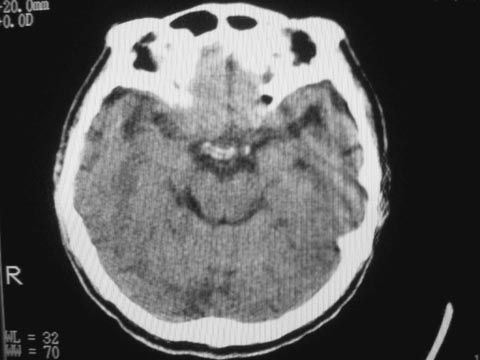

是脑萎缩还是双侧硬膜下积液?

萎缩时脑沟深宽,侧脑池扩大,积液时脑沟变平或不变化。你看看图像,像啥?支持老年脑脑萎缩表现。

左侧基底节区陈旧性脑梗塞、老年性脑改变

支持少量硬膜下积液\\左侧基底节区腔隙性脑梗塞\\脑萎缩.

双侧额、颞部硬膜下积液。

支持脑萎缩,但不能除外合并硬膜下积液。

脑萎缩可能性大,如果是硬膜下积液,邻近脑组织应该是受压的表现。

萎缩时脑沟深宽,侧脑池扩大,积液时脑沟变平或不变化。支持老年脑脑萎缩表现。

脑组织有受压迹象,考虑硬膜下积液。